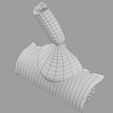

神经肌肉接头示意图